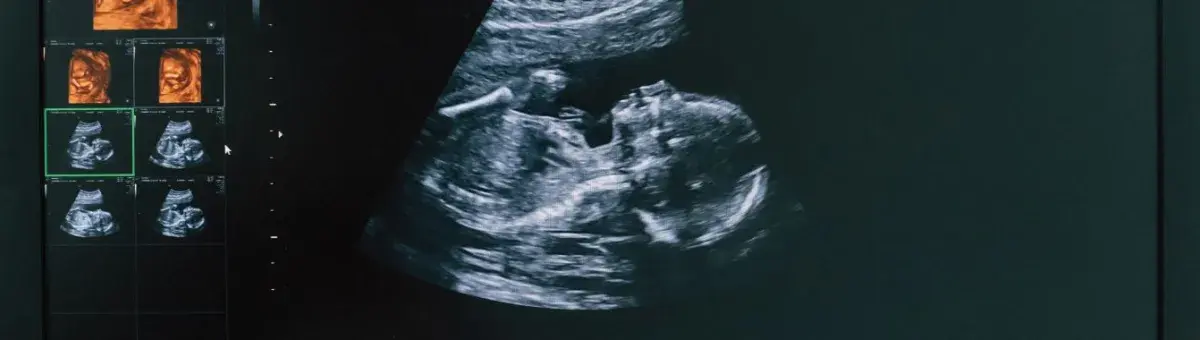

Fetal biometry is a crucial component of prenatal care that involves the measurement of the size and growth of a fetus during pregnancy. Through the use of ultrasound, fetal biometry provides valuable insights into the development of the baby and helps healthcare providers assess if the fetus is growing at a healthy rate. These measurements also play a vital role in detecting potential complications and guiding clinical decisions throughout the pregnancy.

Fetal biometry refers to the process of measuring various parts of the fetus using ultrasound during pregnancy to evaluate fetal growth. These measurements include the size of the baby’s head, abdomen, and femur (thigh bone), and are used to estimate the baby’s weight and assess overall development. Fetal biometry helps track how well the baby is growing inside the womb and can identify growth abnormalities that may need further investigation.

Fetal biometry is typically performed during routine prenatal ultrasounds, especially during the second and third trimesters of pregnancy. These measurements can provide a clearer picture of fetal health and development, helping healthcare providers make informed decisions about the next steps in prenatal care.

Fetal biometry is typically performed through an ultrasound examination. Ultrasound waves are used to create images of the fetus in the womb, which are then analyzed by a healthcare provider to take the necessary measurements. The process is non-invasive and is usually performed on the mother’s abdomen, although in some cases, a transvaginal ultrasound may be necessary.